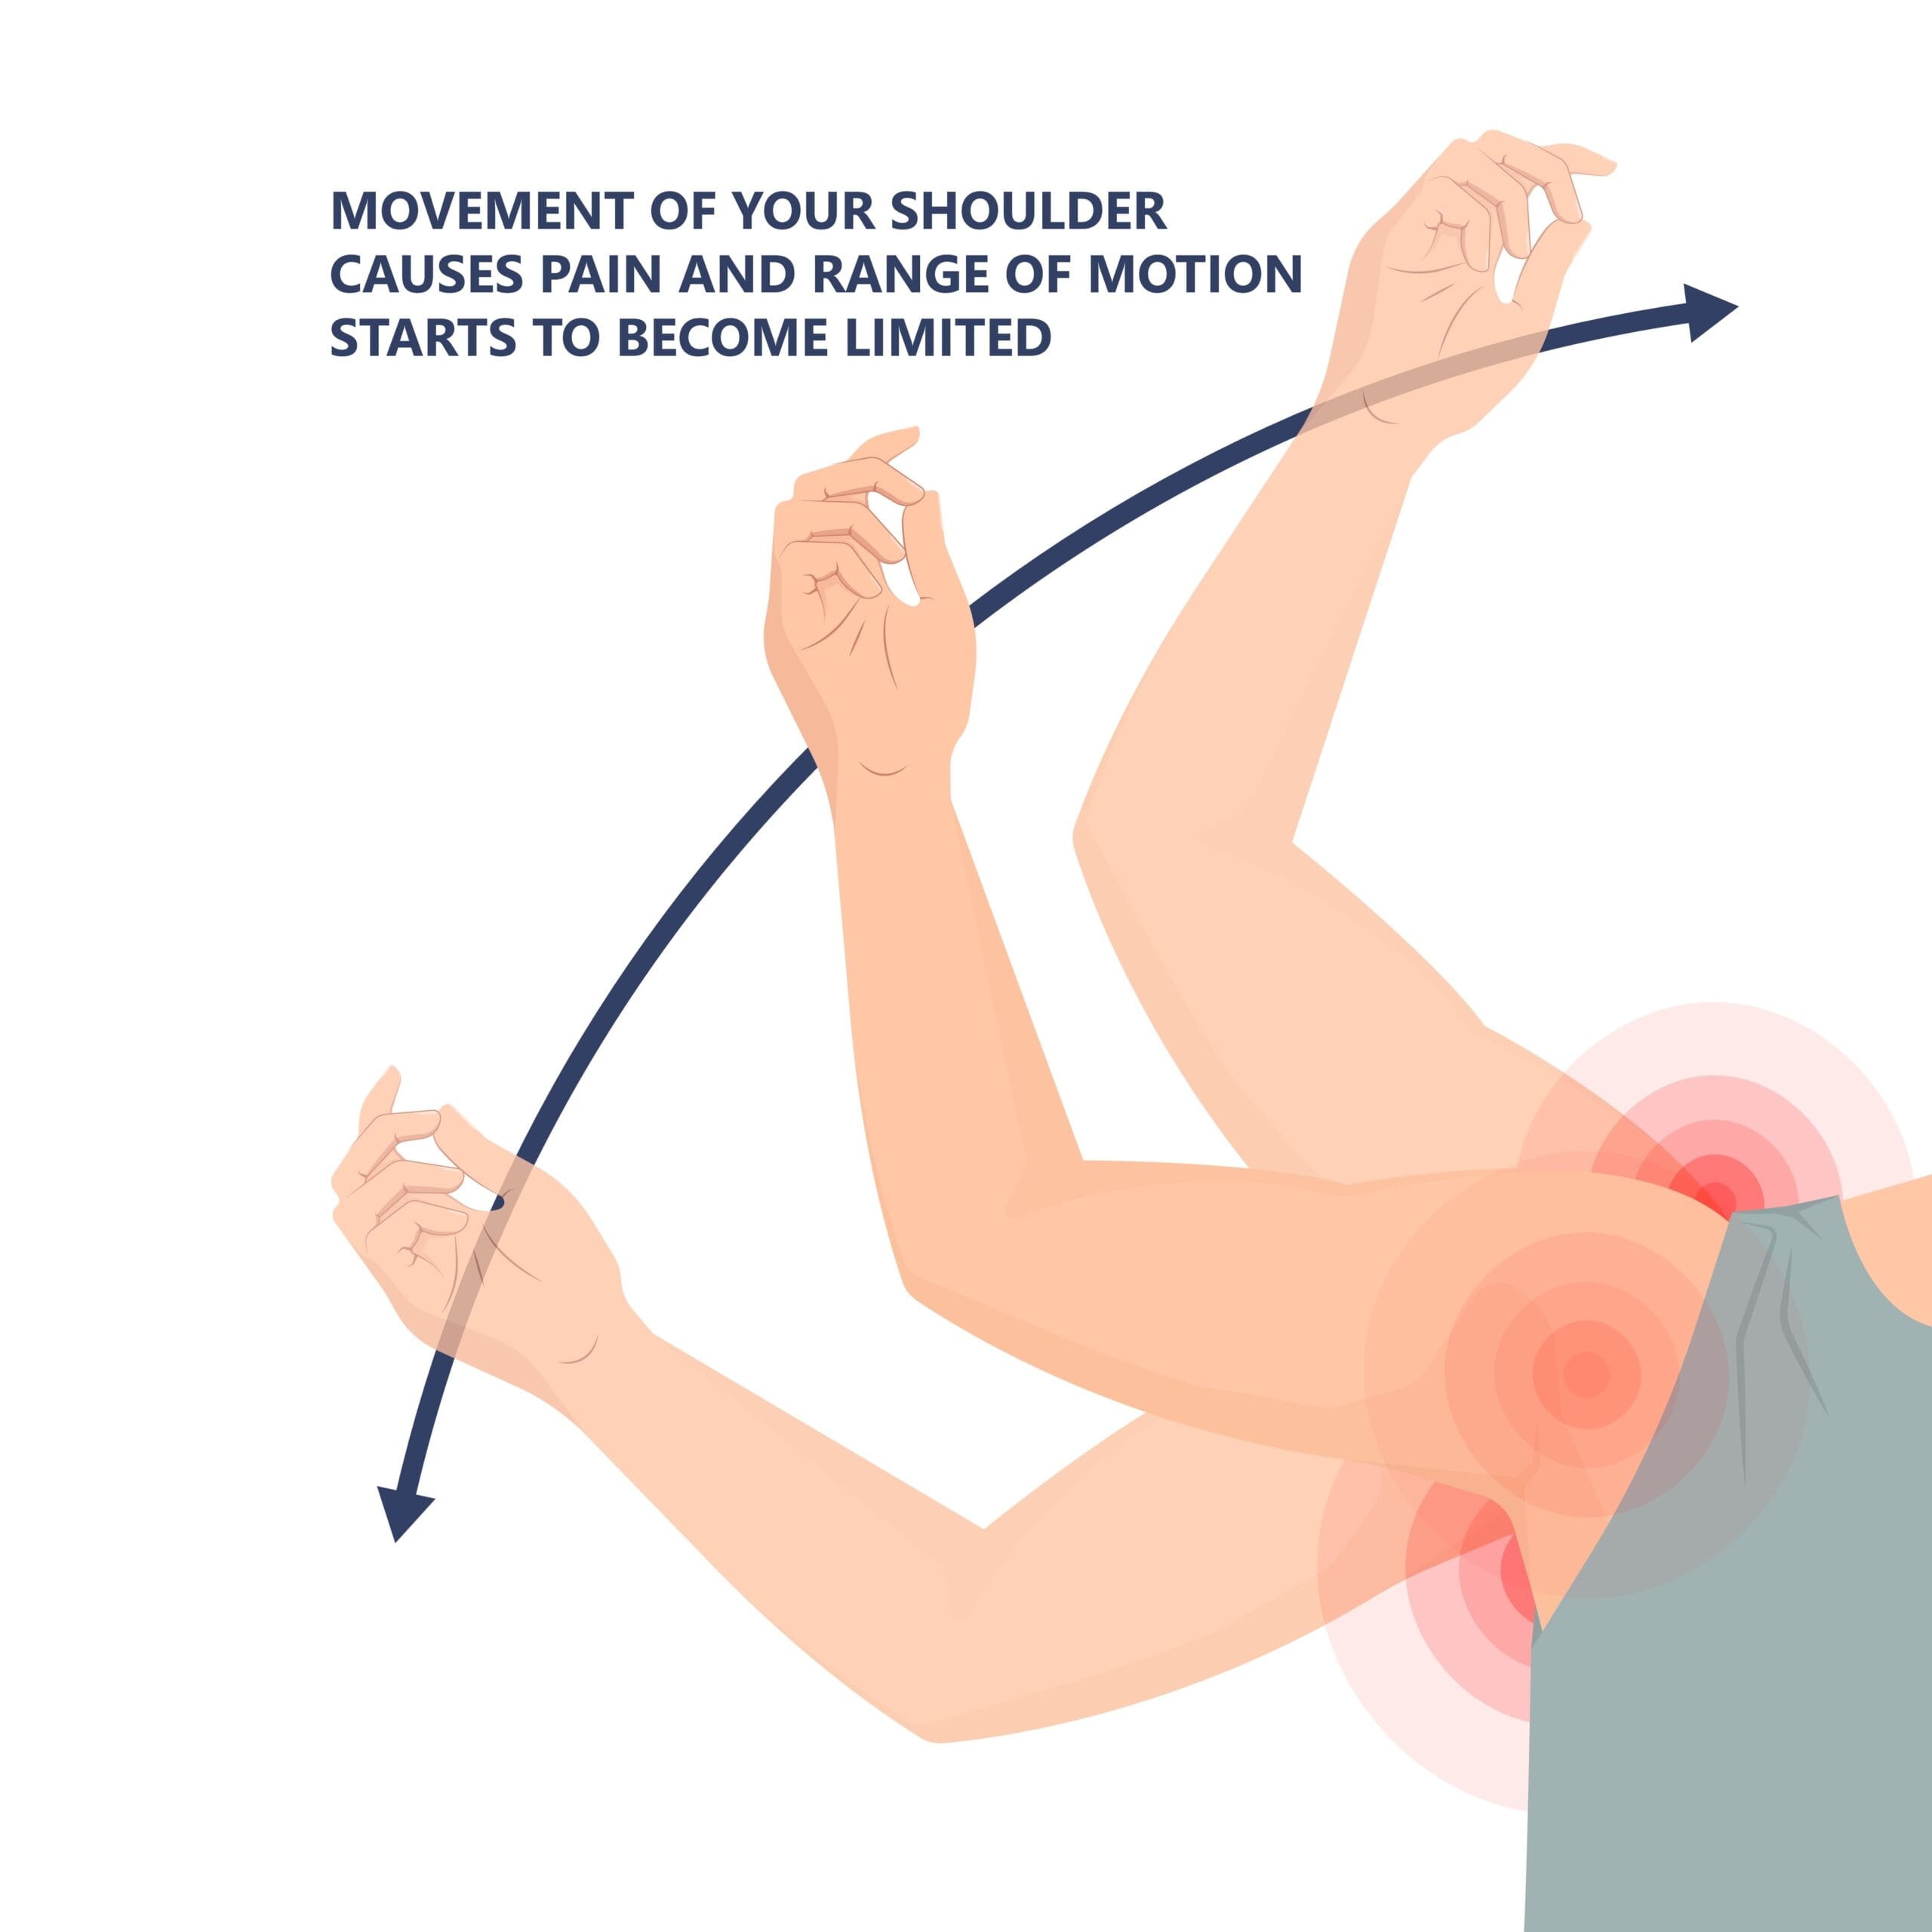

Rotator cuff syndrome (RCS) is a spectrum ranging from minor injuries like acute rotator cuff tendinitis to advanced rotator cuff tendinopathy and degeneration. It usually starts with shoulder pain.

The rotator cuff tendons, especially the supraspinatus tendon, are uniquely susceptible to the compressive forces of impingement. What contributes to rotate cuff pathology includes improper athletic technique, poor posture, less conditioning, and failure of the subacromial bursa. As a result, the supporting tendons progressively get inflamed, calcify, and degenerate leading to a tendon tear.